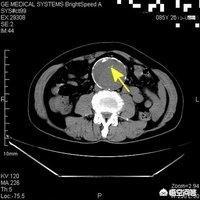

3. examen tomodensitométrique

Le scanner est un peu moins cher que l'IRM pour un site, environ 400+ par site, et environ 1000-1100 si un site est scanné + amélioré. S'il y a deux sites, le coût est plus élevé.

Par exemple, une tomodensitométrie thoracique avec un gating respiratoire coûte environ 500 dollars, et une tomodensitométrie thoracique + rehaussement 1100 dollars.

Si vous effectuez un scanner thoracique + un scanner abdominal, cela représente deux sites, soit environ 1000.

Les IRM et les CT sont tous deux facturés par site, et il n'est pas nécessairement vrai qu'une IRM est plus chère qu'un CT, ou qu'un CT de plusieurs sites est plus cher qu'un seul site.

En outre, l'angiographie par tomodensitométrie (CTA) est plus coûteuse ; elle permet de vérifier les artères par tomodensitométrie (CT), soit environ 2200 pour l'artère coronaire. L'angiographie par tomodensitométrie (CTA) de l'aorte entière, qui permet de voir la longueur maximale du corps, ne pose pas de problème, est d'environ 4200.